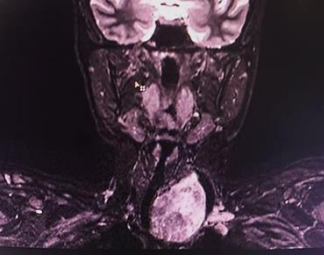

The patient was referred to orthopedician for further evaluation. MRI of the cervical spine with screening whole spine was adviced with some blood investigations. MRIwas suggestive of a large swelling in the left lobe of thyroid with retrosternal extension causing deviation of trachea to the opposite side and compression effect over the structures in the neck.

Figure 1: MRI neck showing left thyroid mass with retrosternal extension deviating trachea towards right and causing compressiveeffects over the structures in the neck.

Blood investigations were send to know the thyroid status. The patient was clinically and biochemically euthyroid. FNAC was done which was inconclusive. The patient was then posted for surgery with intraop frozen section. Intraoperatively a horizontal skin crease incision was taken 4-5 cm above the suprasternal notch. Incision was deepened. Subplatymal planes were created and flaps were raised. Midlinewas seen deviatedtowards the right. Strap muscleswere separated accordingly. Left lobe of thyroid enlarged with lower part extending retrosternal. The retrosternal part was delivered out and left hemithyroidectomy was done. The specimen was sent for intraop frozen section.Frozen section was suggestive of colloid goitre. Post-surgery all the symptoms of the patients got relieved.